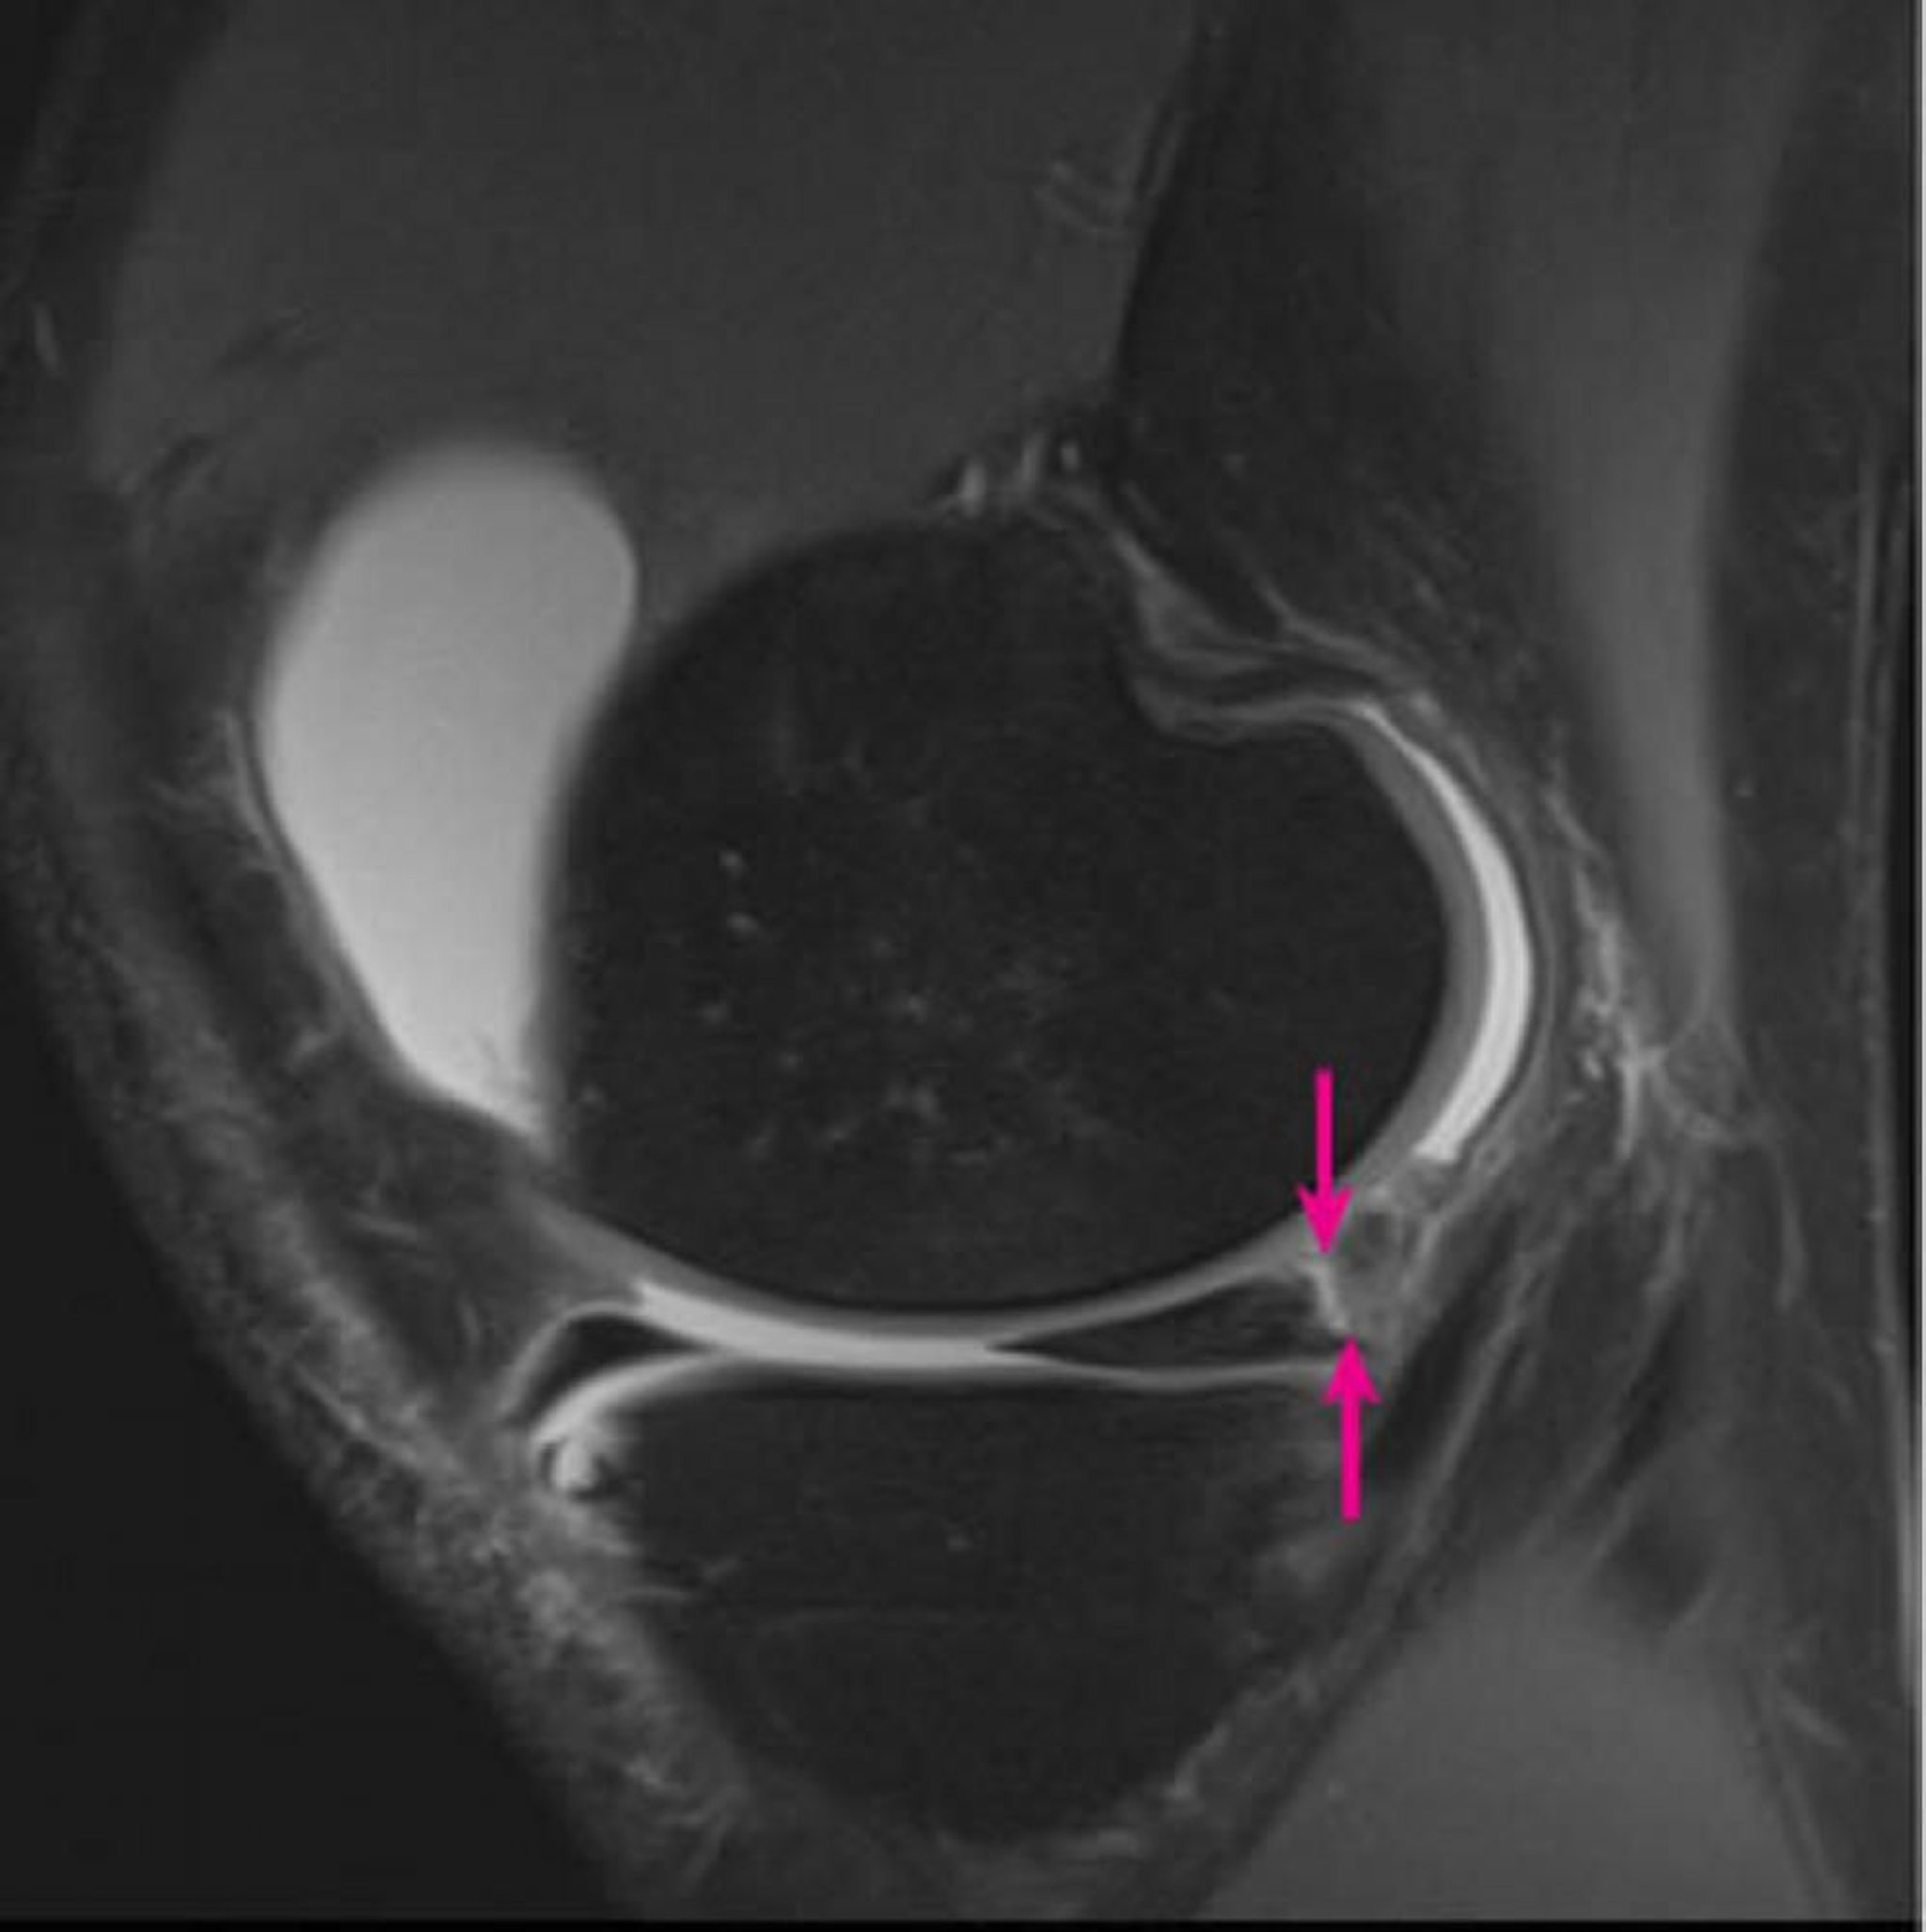

Das sagittale Protonendichte-gewichtete 3-Tesla-Magnetresonanztomographie des rechten Knies zeigt eine Meniskuskapselablösung mit Beteiligung des medialen Meniskus-Hinterhorns (Pfeile).

Image courtesy of Hakan Ilaslan, MD.